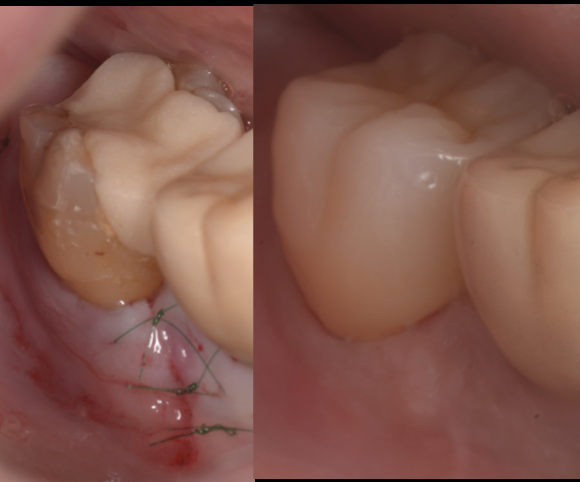

治療前

治療後

~根分岐部病変のリスクと抜歯を回避する最新治療~

池袋院での症例紹介

グランドメゾンデンタルクリニックでは、歯周病専門医がマイクロスコープと歯科用CTを駆使し、根分岐部病変への適切な診断・治療を行っています。